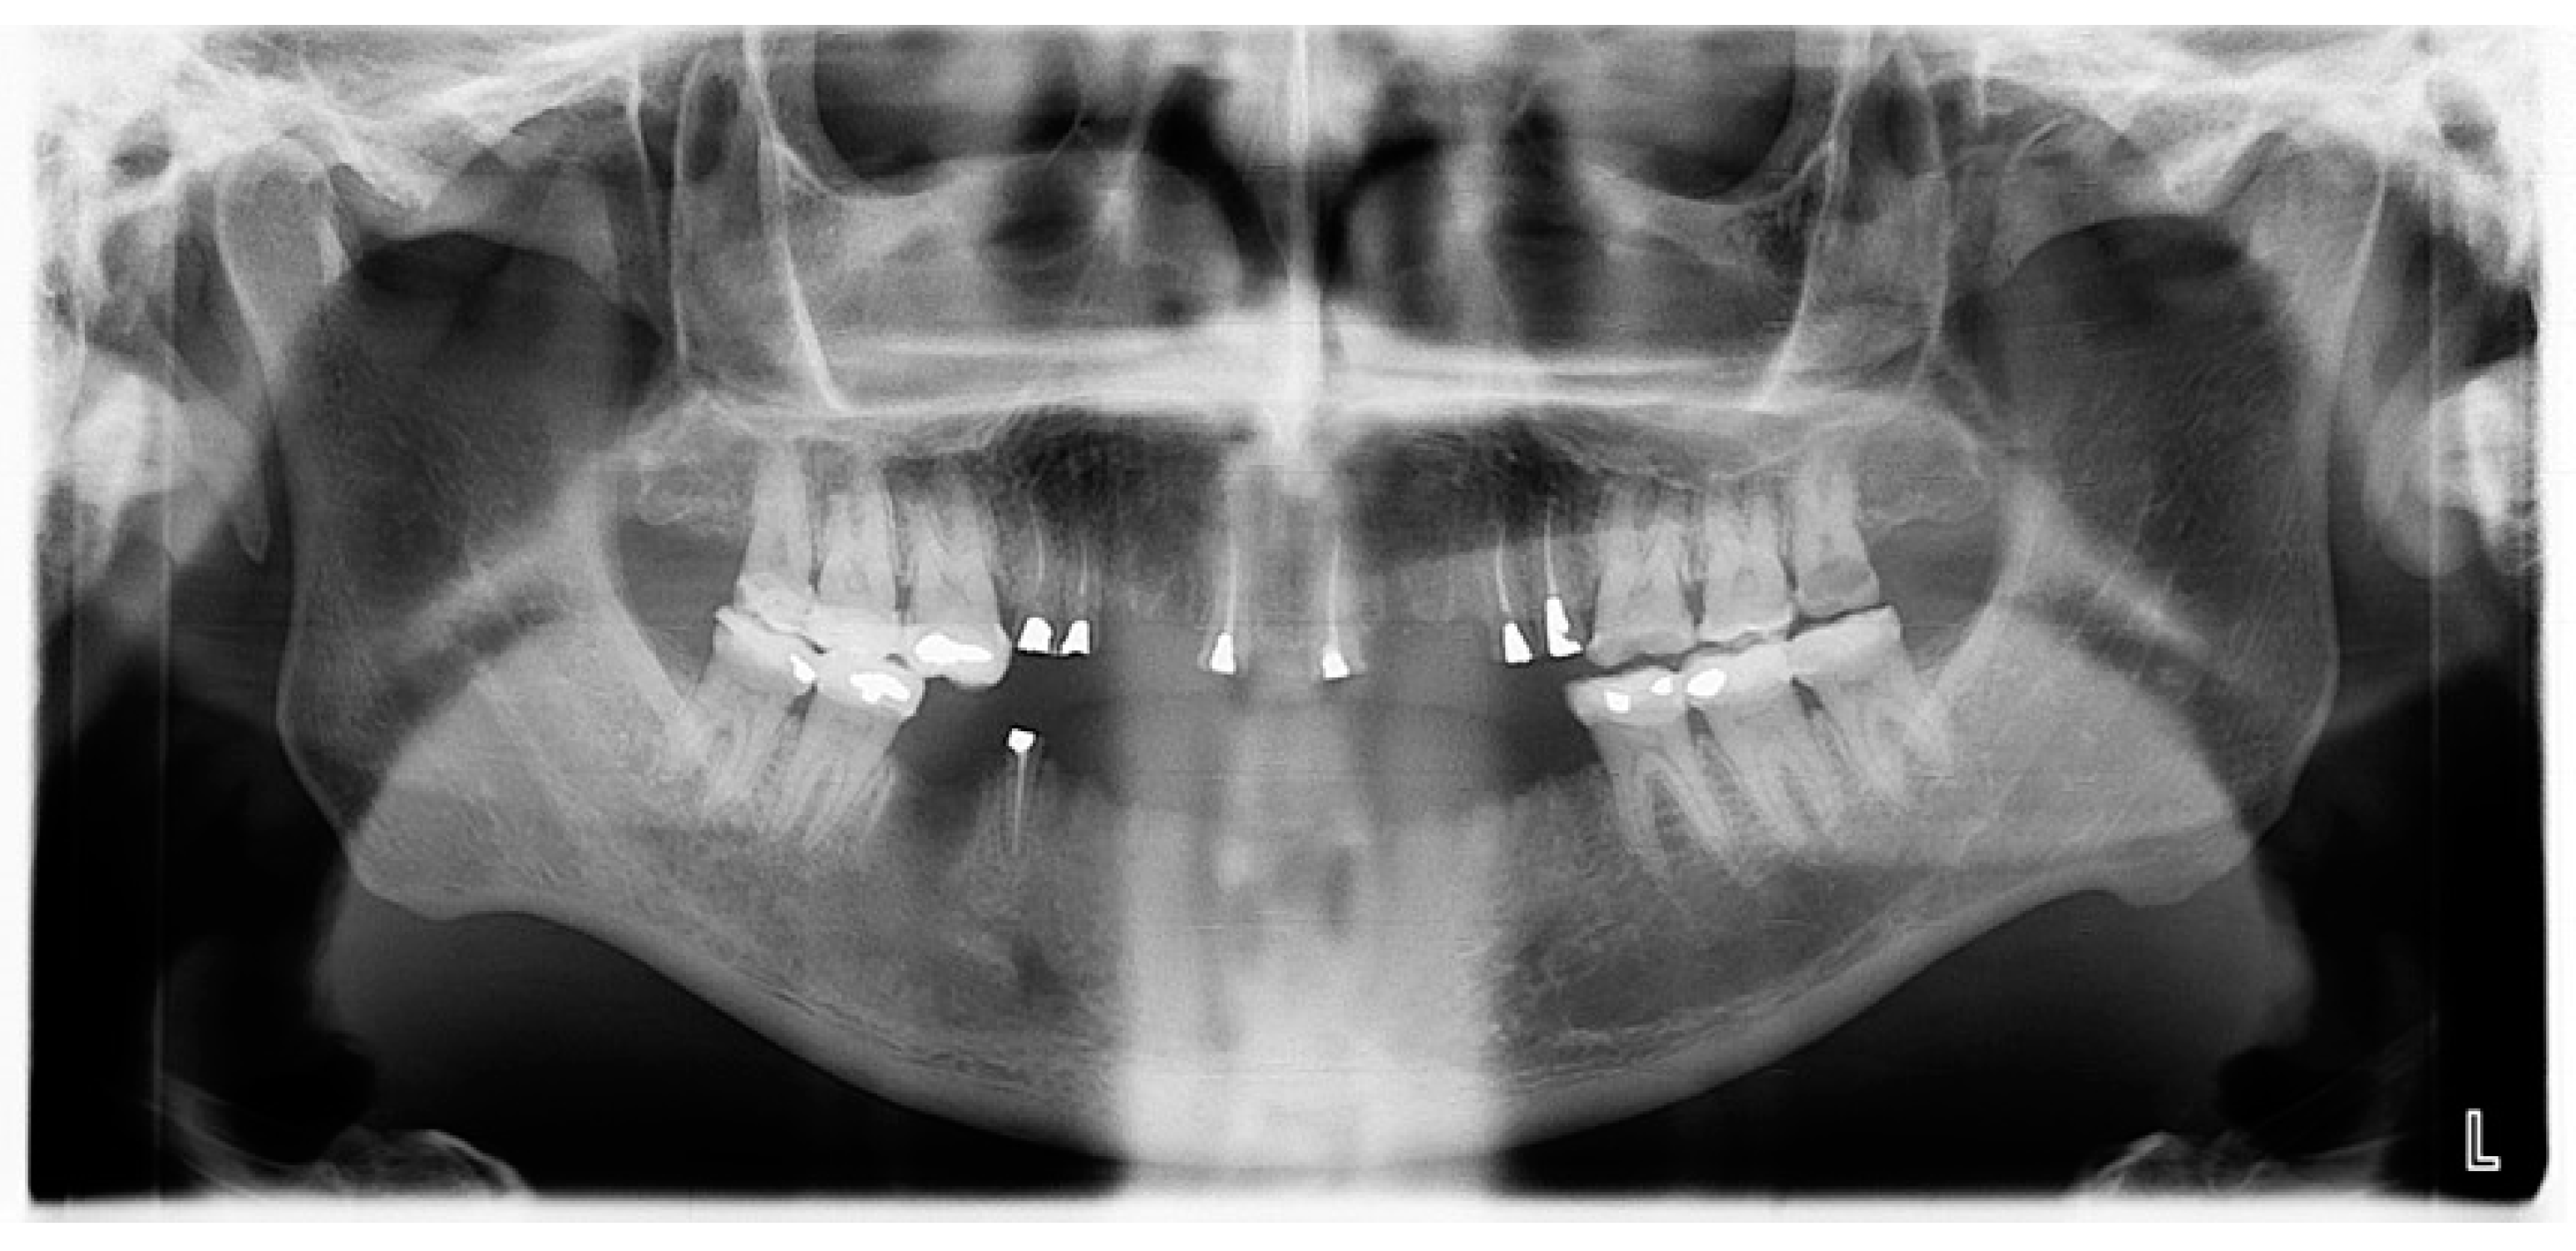

- Pre-prosthetic care: exodontia, endodontic and restorative treatments were performed under general anesthesia. The following procedures were performed: endodontic treatment and bonded amalgam restorations for overdenture abutments of teeth numbers 11, 14, 15, 21, 24, 25 and 45 and exodontia of 46, 44, 43, 41, 33, 34, 35, 23, 22, 13 and 12 (Figure 6). The TRPD were placed on the day of surgery and a postoperative consultation was performed the following day to evaluate and adjust the prostheses (Figure 7).